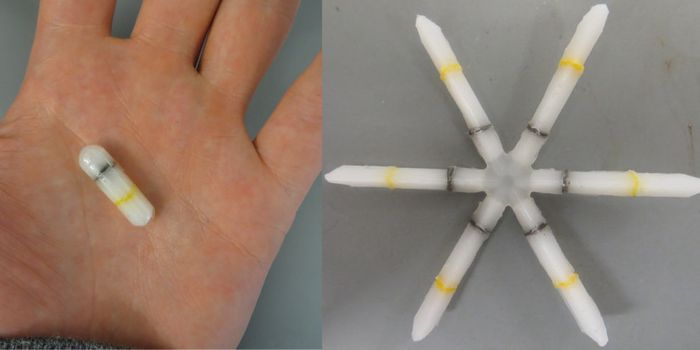

MAY 14, 2023Clinical & Molecular DXScientists have developed a device called CapScan that people can take like a pill, and it will move through the digesti ...